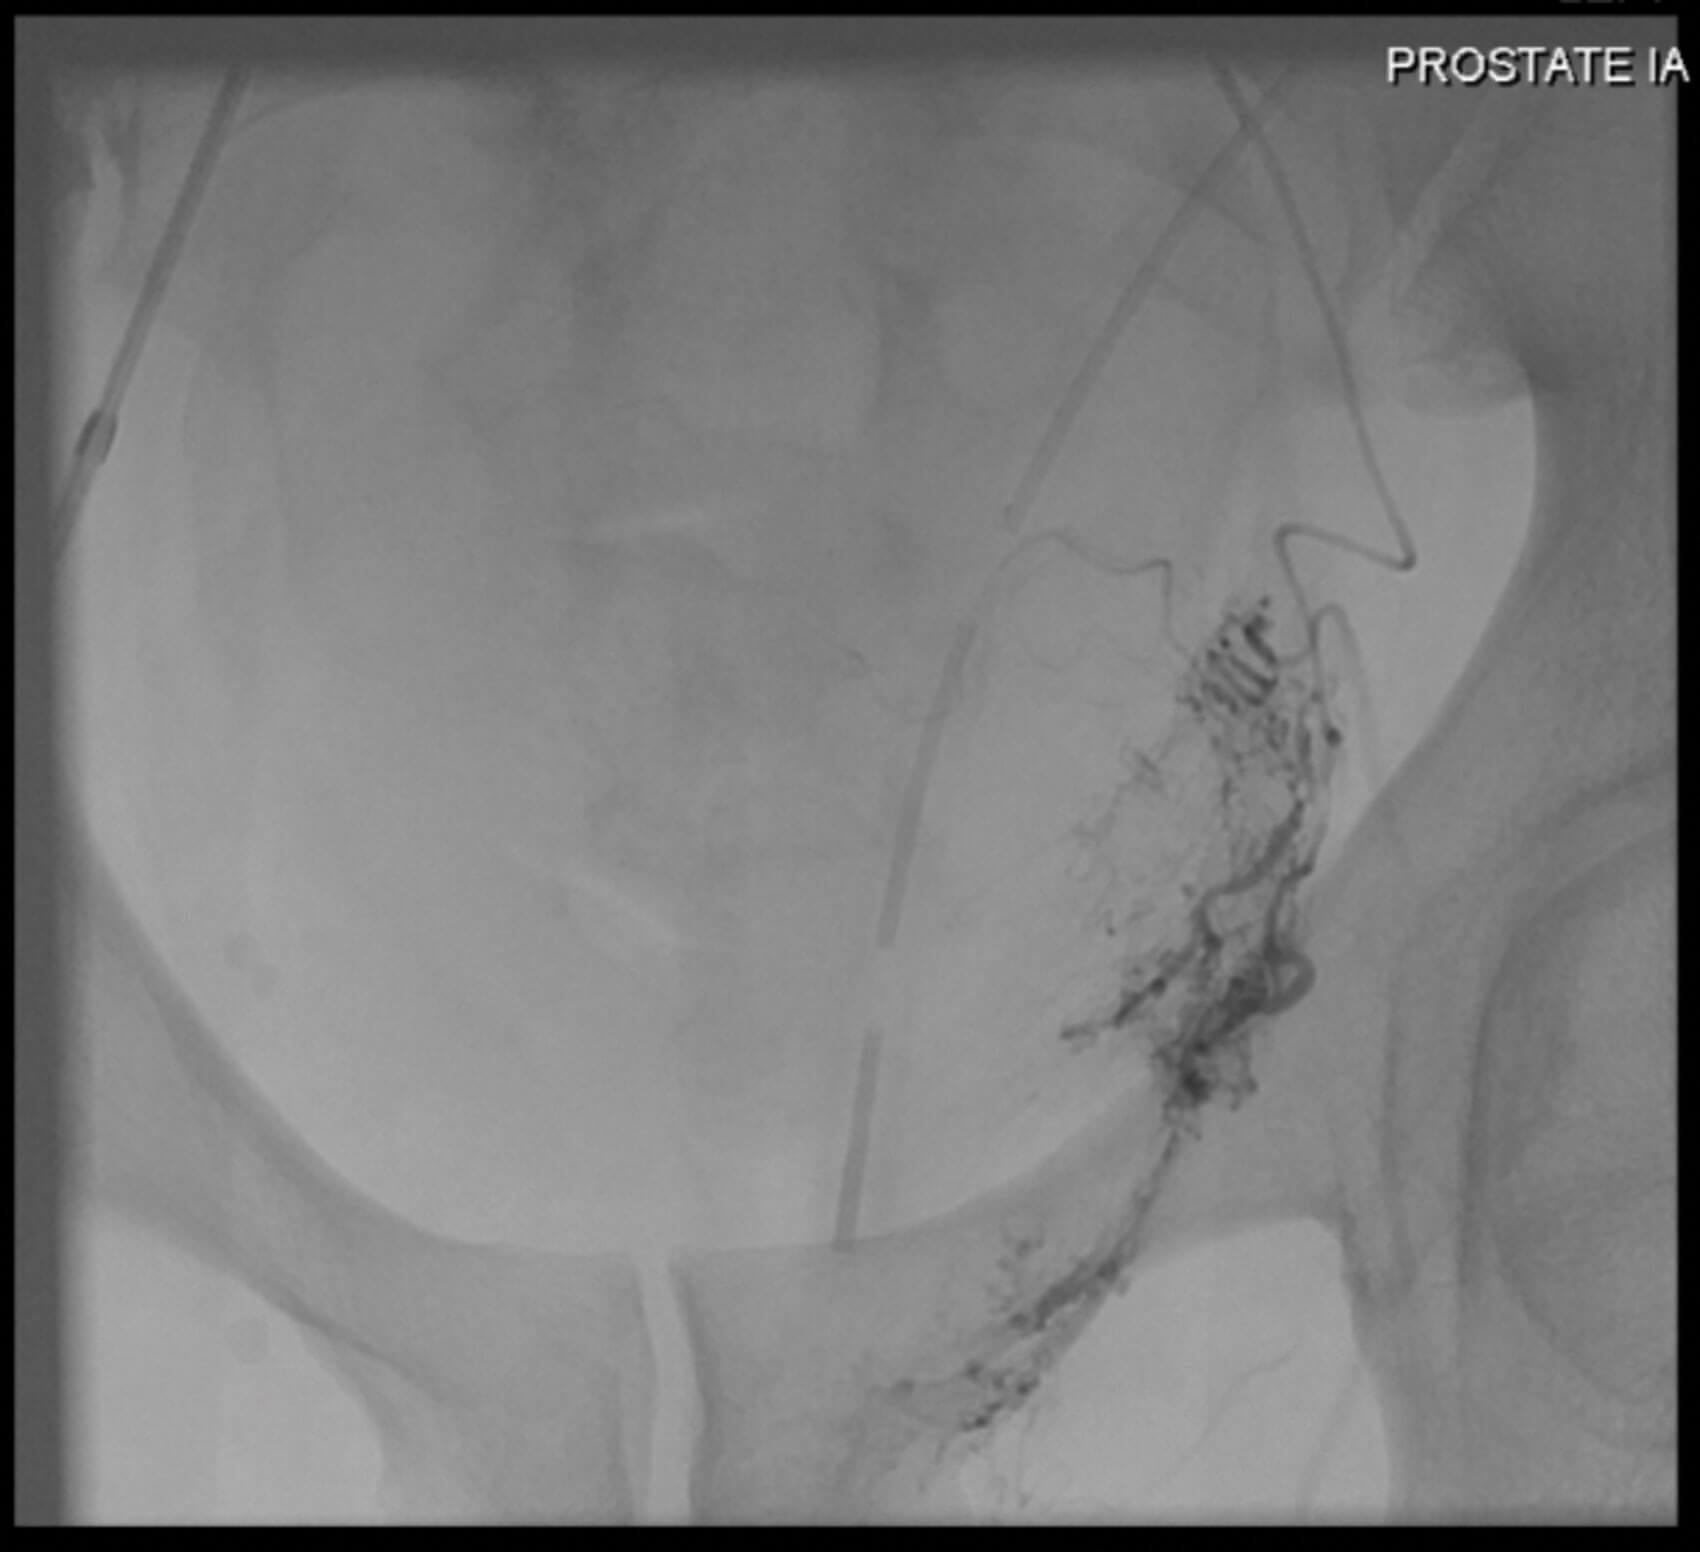

Figure 3: Super-selective embolisation of the residual left prostatic artery by interventional radiology.

The patient underwent robot-assisted radical prostatectomy with a request for bilateral nerve sparing. The operation was very challenging due to fibrotic posterior planes and difficulty in nerve sparing and apical dissection with an estimated blood loss of 300mls. His recovery was complicated by a postoperative bleed causing a pelvic haematoma requiring transfusion and super-selective embolisation of the residual left prostatic artery (Grade III complication, Clavien-Dindo classification) as demonstrated in Figures 2 and 3. The patient experienced transient stress urinary incontinence postoperatively and poor erectile function requiring PDE5 inhibitors and vacuum pump device.